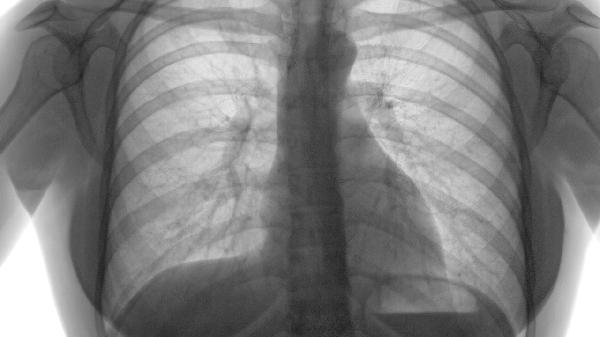

喘病肺气虚耗的中医辨证论治主要包括补益肺气、健脾化痰、温肾纳气等方法,常用方剂有补肺汤、六君子汤、金匮肾气丸等。肺气虚耗型喘病多因久病体虚、劳倦过度或外感失治导致肺气不足,临床表现为气短喘促、声低懒言、易感外邪等症状。